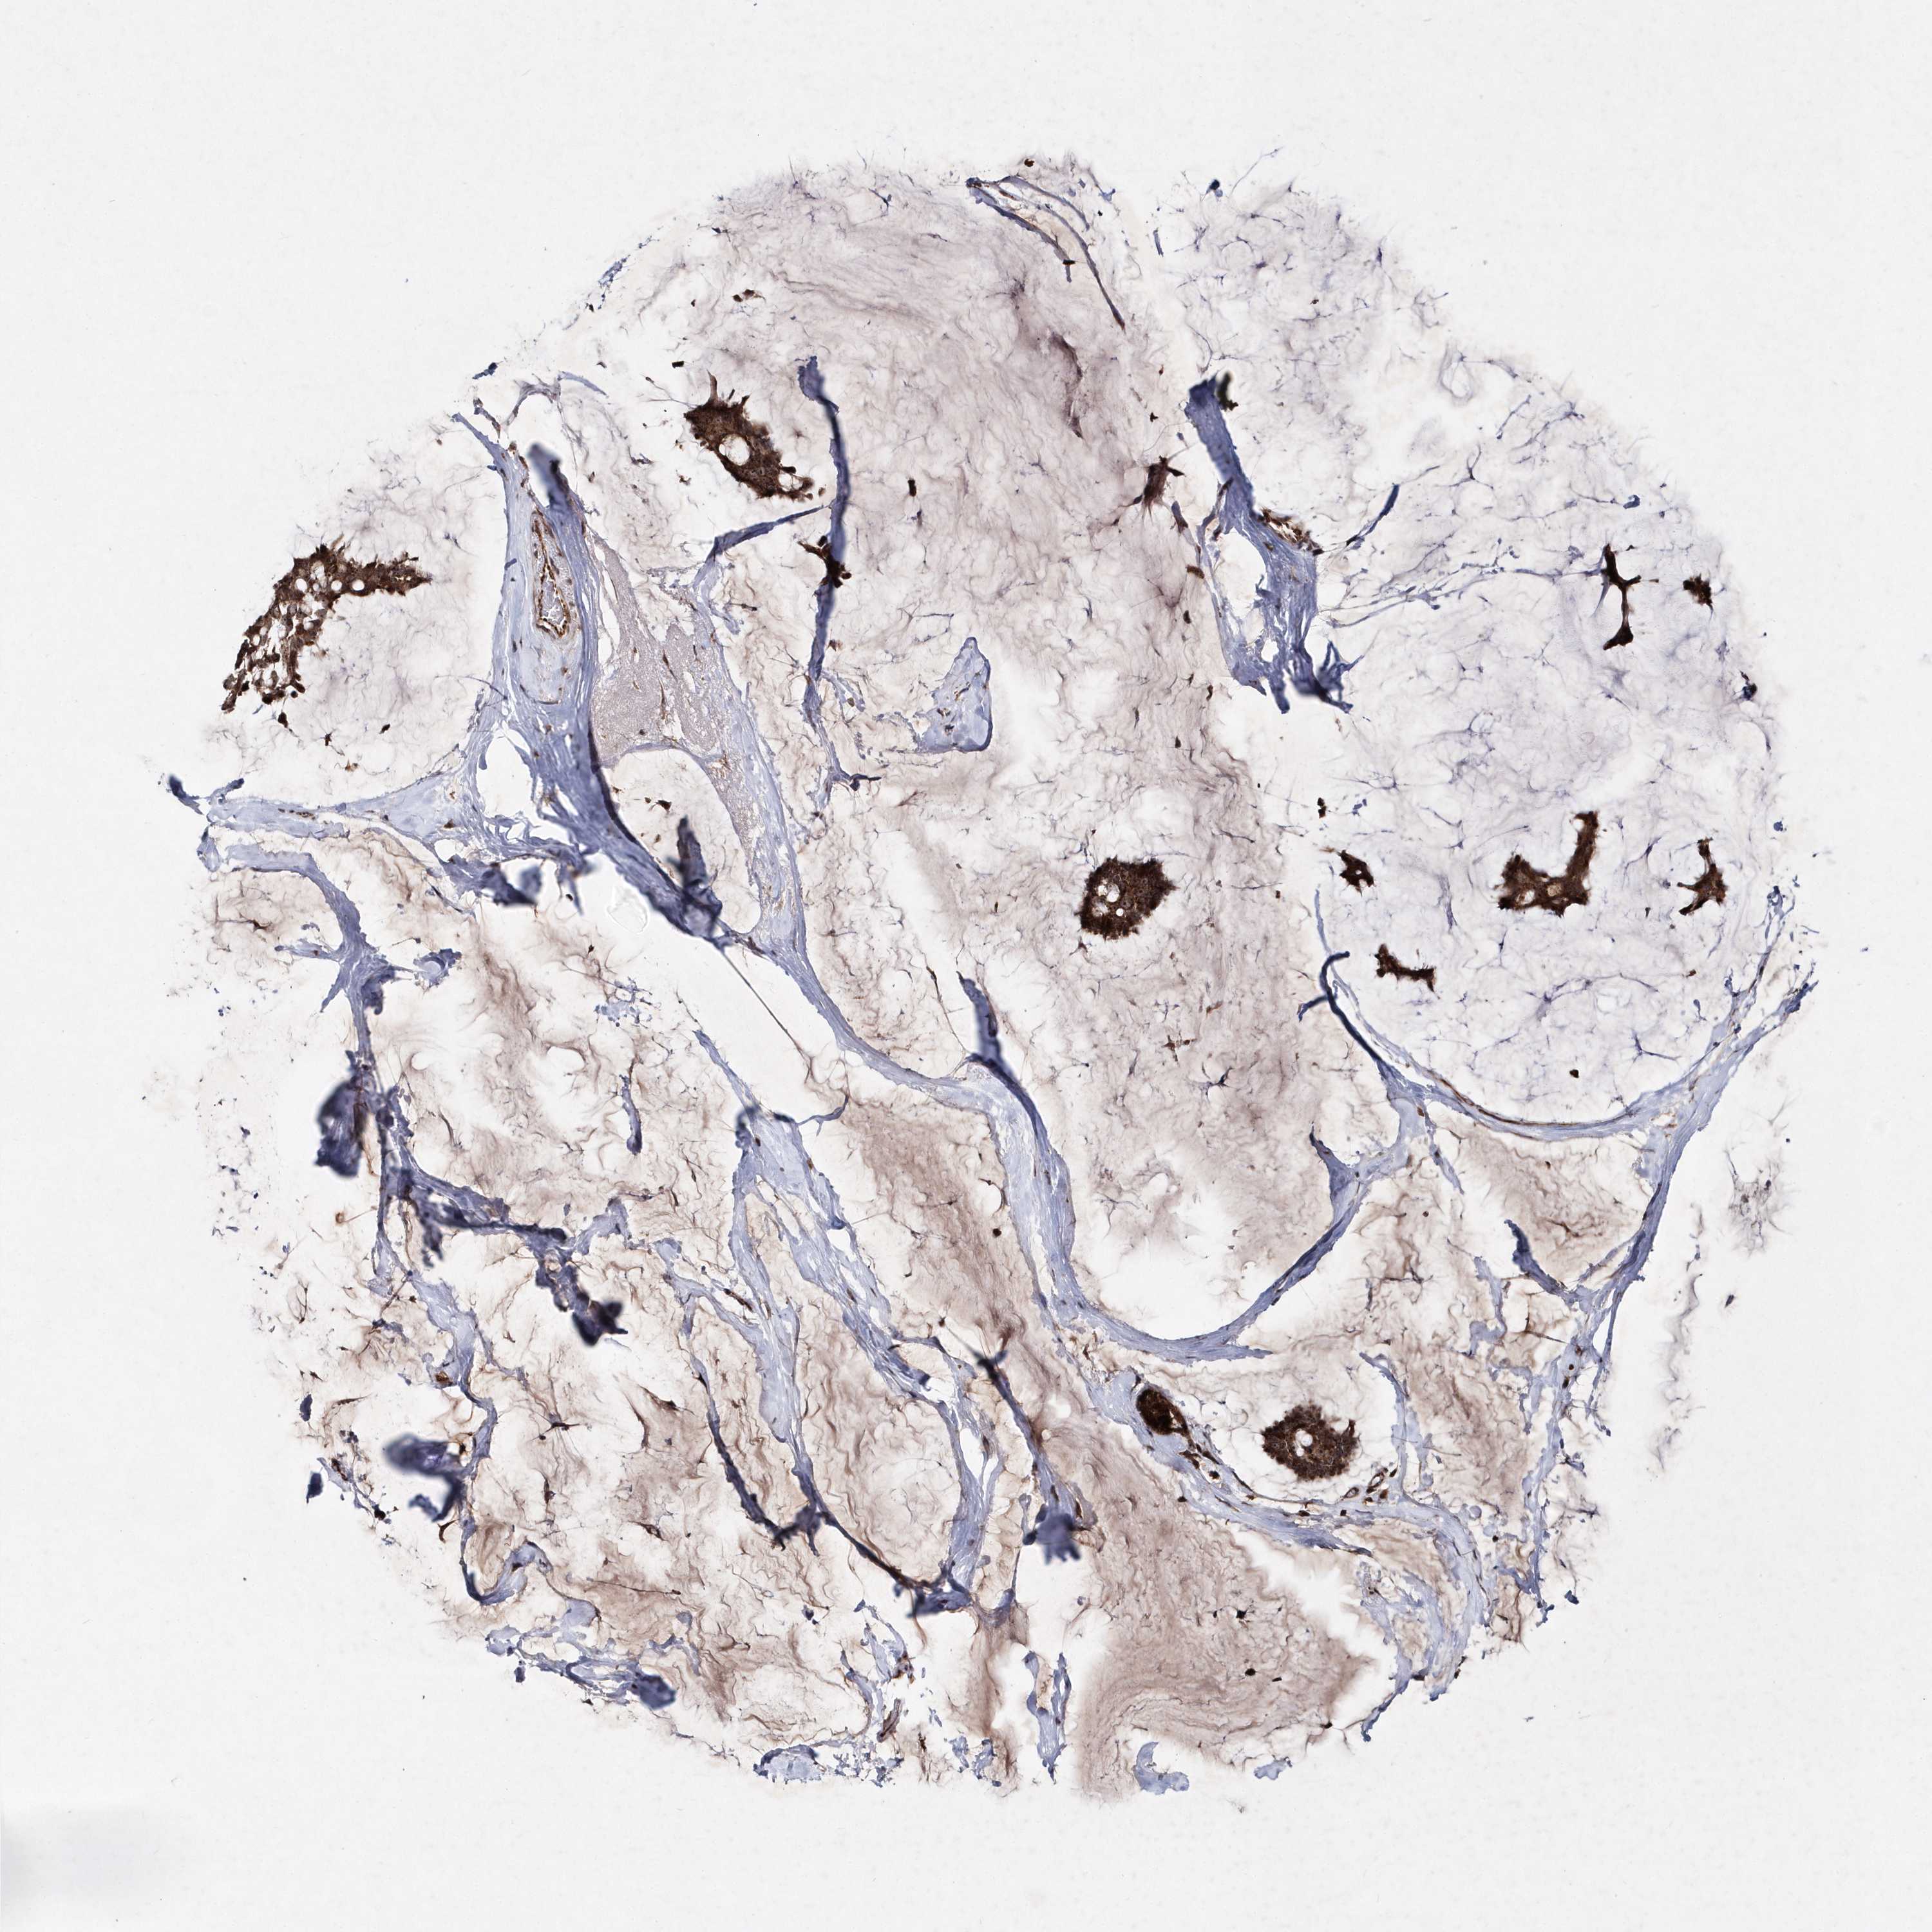

CANCER BREAST CANCER Show tissue menu

Breast cancer

Human cancer